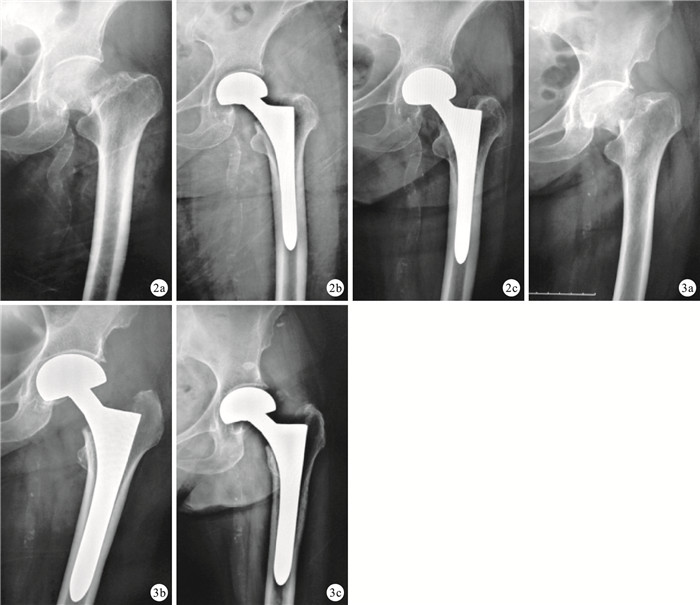

術后60 d X線片測量示,A、B組雙側偏心距差距分別為(2.23±1.78)、(2.41±0.93)mm,雙下肢長度差分別為(3.29±1.92)、(3.11±2.07)mm,比較差異均無統計學意義(t=1.273,P=0.851;t=0.409,P=0.327)。A、B組假體柄力線良好率分別為82.86%(29/35)、85.29%(29/34),比較差異無統計學意義(χ2=0.584,P=0.497)。隨訪期間兩組均無假體松動發生。見圖 2、3。

有學者認為微創關節置換術中暴露不良,會增加假體正確放置難度[16-17]。本研究術后影像學觀測提示,根據假體力線評價結果,A組82.86%、B組85.30%患者假體位置良好,差異無統計學意義;且兩組雙下肢長度及偏心距差距亦均無顯著性差異。提示微創手術入路只要應用得當,對于假體安放影響不大,這與Alecci等[18]的觀點一致。